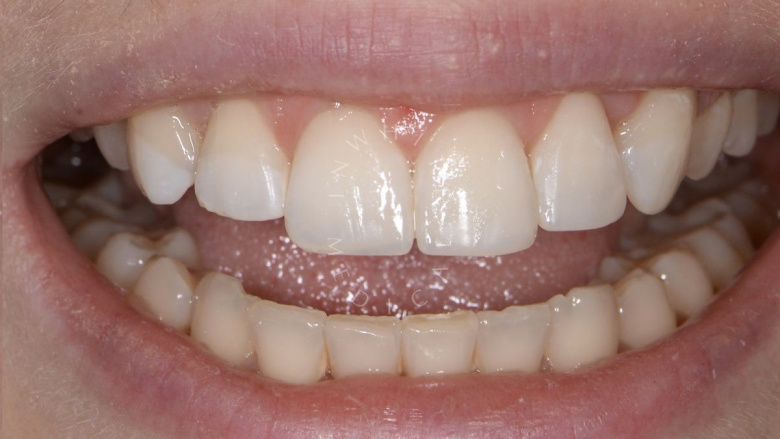

Результат

Стоматология Москва лучшие клиники. Лечение фиссурного кариеса под увеличением - до процедуры

Стоматология Москва лучшие клиники. Лечение фиссурного кариеса под увеличением - после процедуры

До После